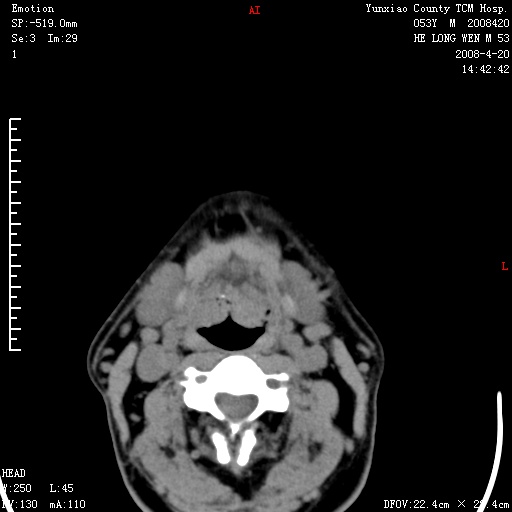

双侧扁桃体肿大:考虑化脓性扁桃体炎。

双侧扁桃体肿大 ,考虑扁桃体炎。

双侧扁桃体肿大,建议结合临床!

双侧扁桃体肿大 ,考虑扁桃体炎

能强化就强化,不能强化就喉镜检查。如怀疑扁桃体肿大,应再往上扫

应该有症状,体检此部位不是常规体检项目,支持双侧扁桃体肿大 ,考虑扁桃体炎,但还是强化一下吧。

双侧扁桃体肿大,考虑扁桃体炎,应做一下增强

显示部分为舌扁桃体,腭扁桃体未见显示。会厌显示欠规则,建议喉镜。